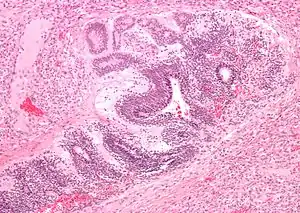

Micrograph of the primitive neuroepithelium of an immature teratoma of the mediastinum. H&E stain.